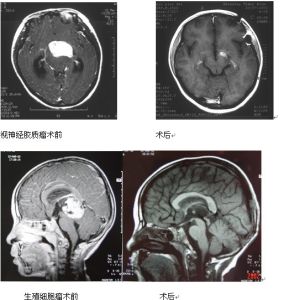

腦角質瘤腦膠質瘤是目前最常見的顱內惡性腫瘤之一,約占顱內腫瘤的40%~50%,由於腫瘤生長呈浸潤性,傳統的治療難以切除,容易復發。我科從2000年6月—2006年6月共收治379例,根據腫瘤部位及大小,除採用傳統治療外,結合化療、放療等方法,明顯提高了患者生存率,現總結報告如下。

幕上非重要功能區惡性膠質瘤

一般採取腫瘤大部切除,術中在殘瘤腔內置入自行研製的放療囊和化療囊,術後進行抗核型單抗標載的131I免疫導向放療、瘤內間質化療、瘤腔內131I或125I近距離放療。另外,根據腫瘤病理免疫組化提示的藥敏標記物,採用經頸總動脈、經股動脈-頸內動脈選擇性或超選擇性介入化療。

囊性膠質瘤

採用立體定向或徒手定向技術置入化療囊,術後進行抗核型單抗標載的131I免疫導向放療。同時根據腫瘤活檢的免疫組化提示的藥敏標記物,採用經頸總動脈、經股動脈-頸內動脈或椎動脈的選擇性/超選擇介入化療。

小腦惡性膠質瘤

採用手術切除後,在腫瘤殘腔內置入自行研製的化療囊,術後進行免疫導向放療。同時,選擇對腦後循環刺激輕微的化療藥(如仍沿用),進行經股動脈-椎動脈選擇性或超選擇性介入化療。

按傳統的綜合治療,多數患者接受外科手術後會出現兩種結局:一是術後重要的神經功能缺失,如偏癱、失語和視丘下部損害;二是手術的刺激會造成腫瘤惡性程度增高,實際上縮短了病人生存期。接診的神經外科醫師在沒有把握從根本上控制腫瘤增殖或治癒腫瘤的情況下,貿然手術切除實際是亂捅“馬蜂窩”,後果是造成復發後腫瘤浸潤範圍廣泛、瘤細胞惡性程度增高。因此腦膠質瘤的第一次治療方案應慎之又慎,不能貿然手術切除。我們根據丘腦或基底節區星形細胞瘤區域多數腫瘤生長緩慢、分化程度較高,可以長時間(5年之內)生存的特點,設計立體定向輔助下腫瘤131I組織間液放療,能取得良好治療效果。

我們根據患者全身情況、年齡、腫瘤部位、性質和特點將膠質瘤分為7個治療類型:大腦半球、小腦半球、腦幹、囊性、腦深部、幕上低級別和小兒的膠質瘤。又分別採取7種新綜合治療方法:即術後瘤內間質化療、術後瘤內近距離放療、術後經腦動脈介入化療、非高顱壓狀態下單純經腦動脈介入化療、免疫導向放療、瘤組織間液放療、外周血造血幹細胞支持下的大劑量化療等7項新技術。精心擬定39種組合治療方案進行個體化治療,改變了腦膠質瘤傳統治療的弊端。